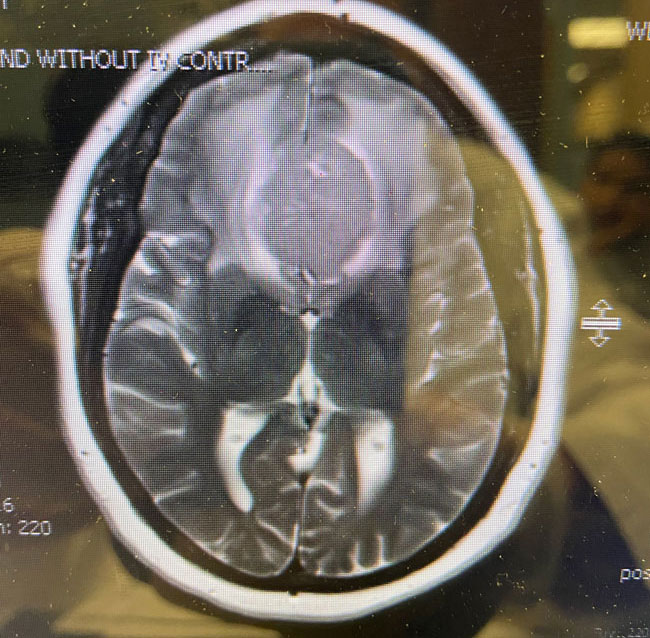

This is a 64 year-old woman with no significant past medical history who noted rapid deterioration of vision in her left eye 3 weeks earlier. She said it felt like there was a cloud over her eye. Ophthalmology evaluation confirmed poor vision in the left eye and ordered a brain MRI. The MRI demonstrated a large planum sphenoidale meningioma with significant compression on the optic nerves and optic chiasm and significant surrounding edema (Figures 1 a, b, and c). She was then referred to Dr. Michael Brisman for neurosurgical evaluation.

Dr. Brisman started the patient on steroids to reduce the surrounding edema. After a few days, the patient did note some improvement in her vision. Due to the size of the tumor, the amount of edema, the rapid progression of symptoms, the patient was scheduled for surgery.